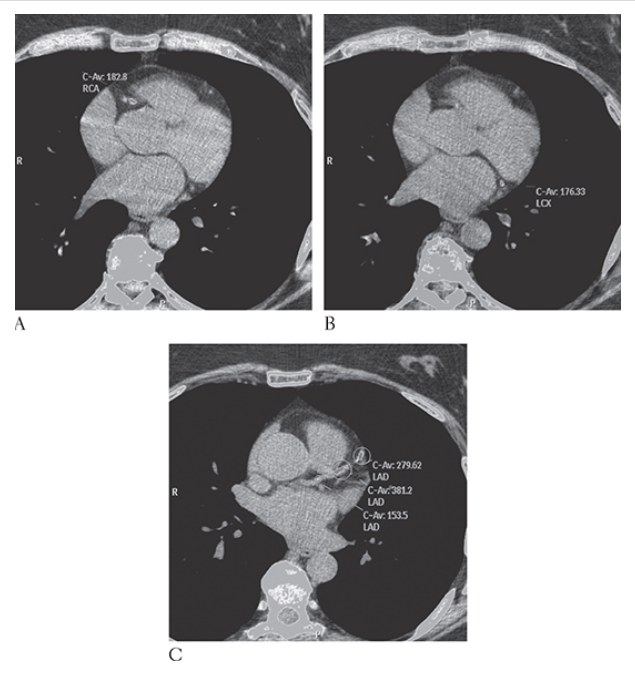

What is A

Coronary Artery Disease. Nonenhanced CT (NECT) shows computer-aided detection and calculation of coronary artery calcification in the right coronary artery left circumflex artery

What is B

Coronary Artery Disease. Nonenhanced CT (NECT) shows computer-aided detection and calculation of coronary artery calcification in the right coronary artery and left anterior descending coronary artery

What is C

Coronary Artery Disease. Nonenhanced CT (NECT) shows computer-aided detection and calculation of coronary artery calcification in the right coronary artery